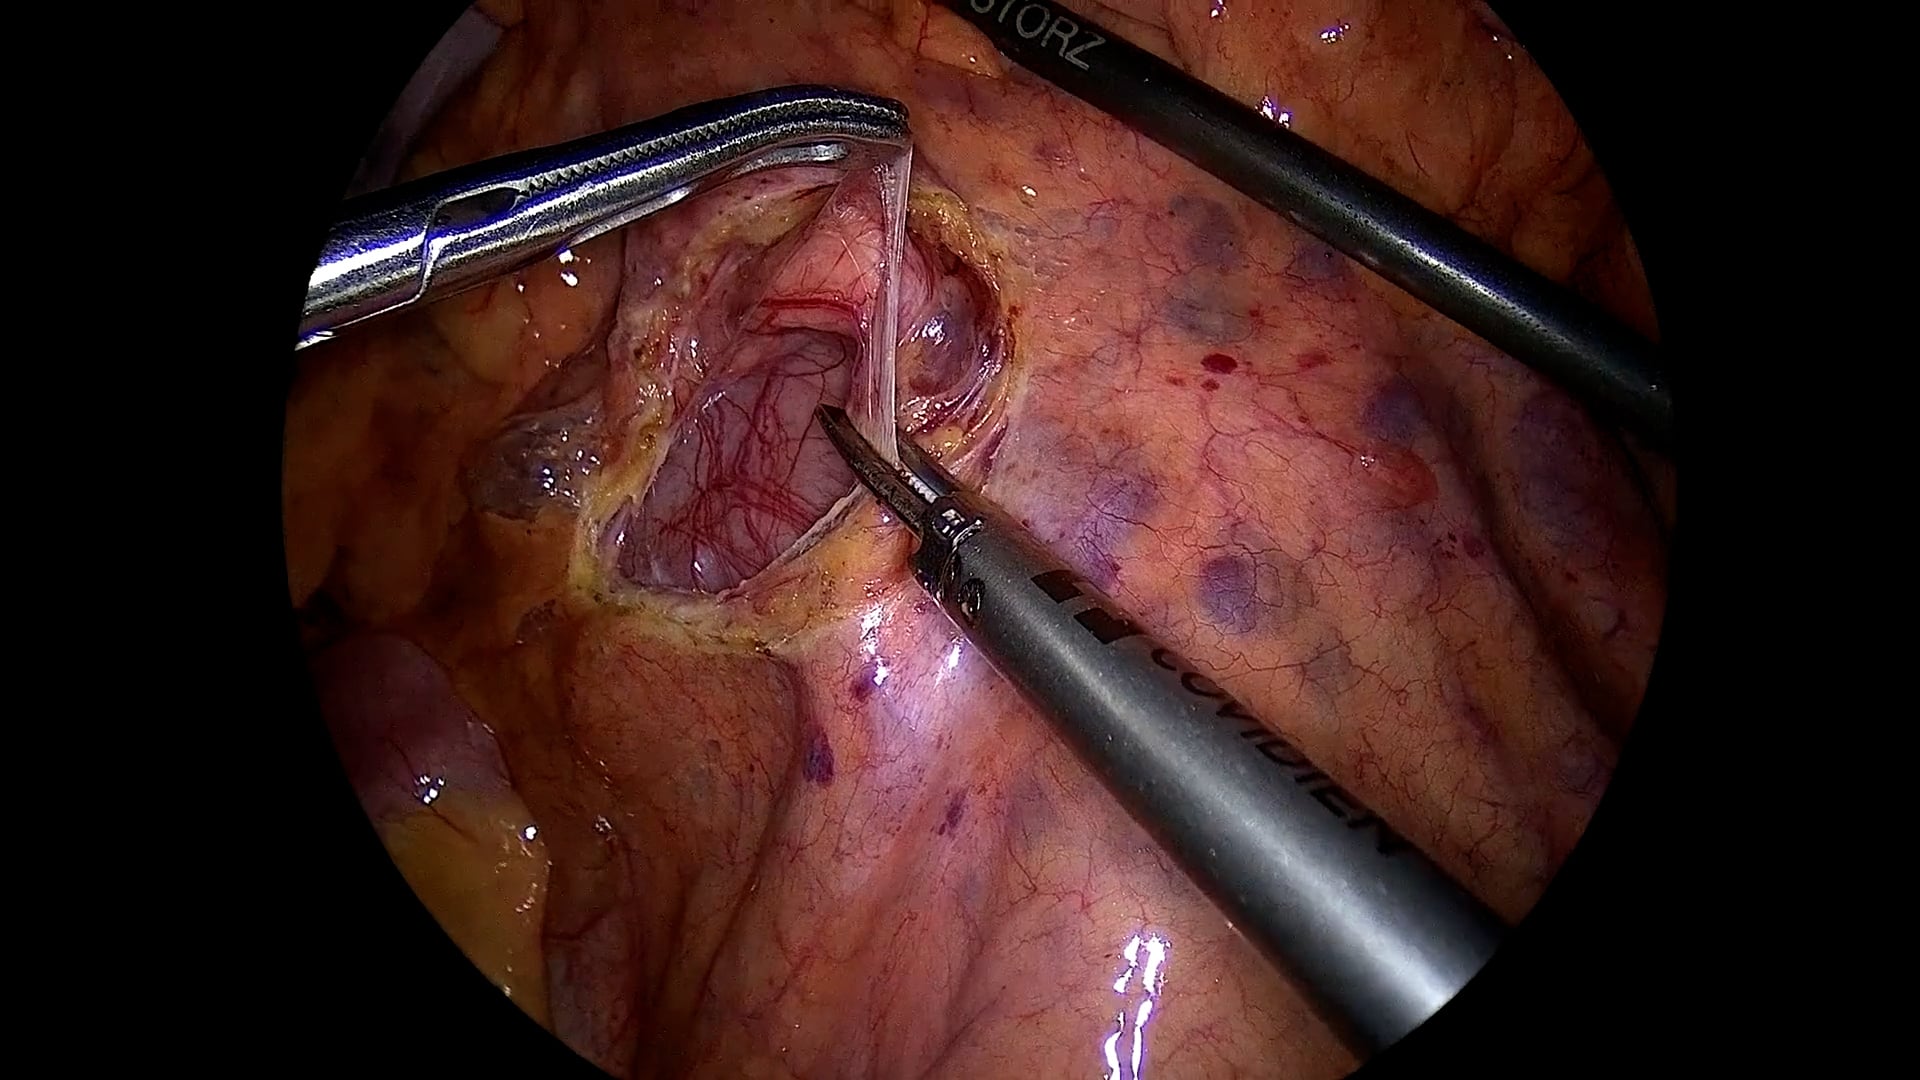

Laparoscopic surgery

IRCAD offers a variety of courses in laparoscopic surgery. The theoretical and hands-on training will allow you to perfect your skills, under the supervision of the world’s top experts in many different specialties. Register to one of our courses today!